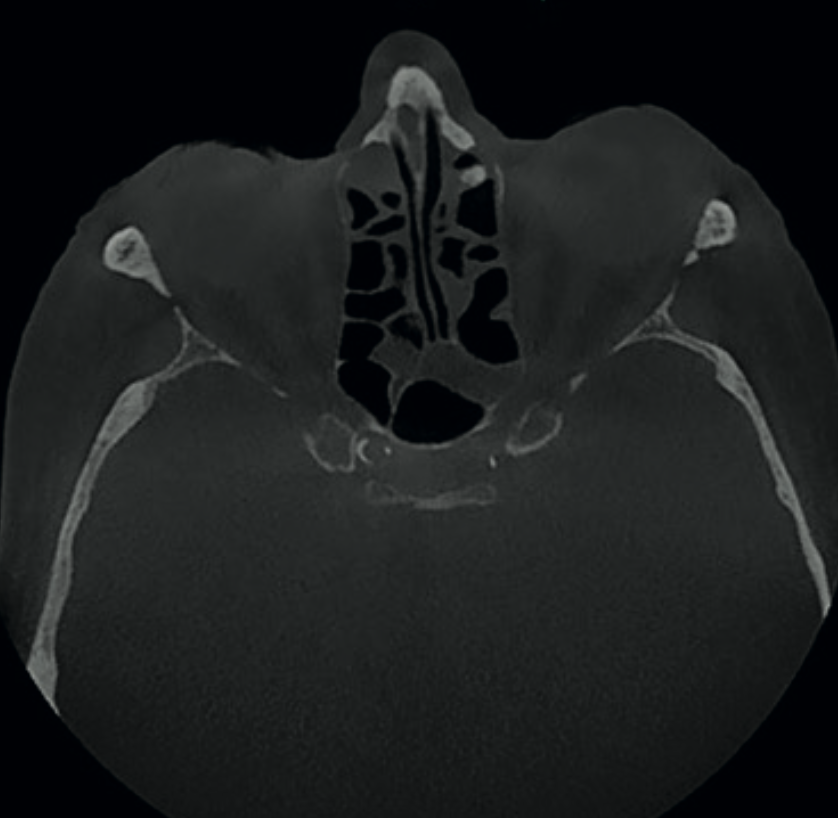

Axial CBCT view showing enlarged incisive foramen suggestive of incisive canal cyst

Finding 1

Enlarged incisive foramen

Larger than usual dimensions on the axial view, possibly indicating an incisive canal cyst. If symptomatic or progressive, this would require surgical intervention.